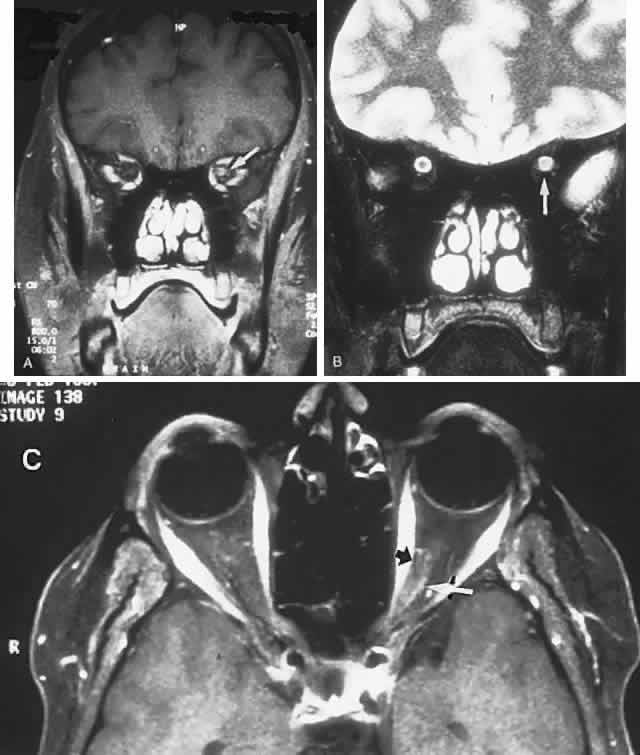

CONGENITAL HAMARTOMA SYNDROMES

The “neurophakomatoses” are a diverse group of disorders nosologically related by the presence of hamartomatous lesions, and, indeed, the term “hereditary hamartomatosis” is a more accurate description. However, whereas neurofibromatosis, tuberous sclerosis, and von Hippel-Lindau disease are transmitted with irregular dominance and considerable variation in penetrance, no hereditary basis of Sturge-Weber or angio-osteohypertrophy (Klippel-Trenaunay-Weber) syndrome has been established.